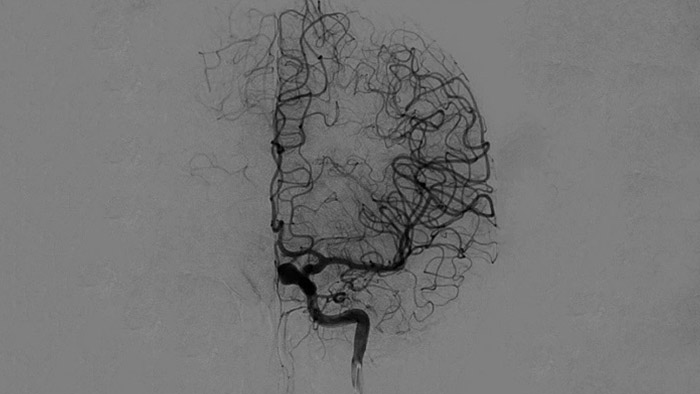

Visualisation d’angiographie par soustraction numérique (ASN)

Les visualisations d’angiographie par soustraction numérique (ASN) de haute qualité vous permettent d’évaluer si vous avez retiré le caillot complet et si des morceaux de caillot ont été dispersés de manière distale dans le cerveau. Vous pouvez vérifier le rétablissement du débit sanguin dans la pénombre et contrôler les hémorragies péri-procédurales.

Améliorez la visualisation des vaisseaux

Roadmap Pro

Prenez des décisions éclairées concernant l’accessibilité du caillot et la voie à utiliser. Roadmap Pro est une cartographie avancée à double contraste, permettant d’améliorer la visualisation des vaisseaux superposés, tout en équilibrant l’exposition au rayonnement.